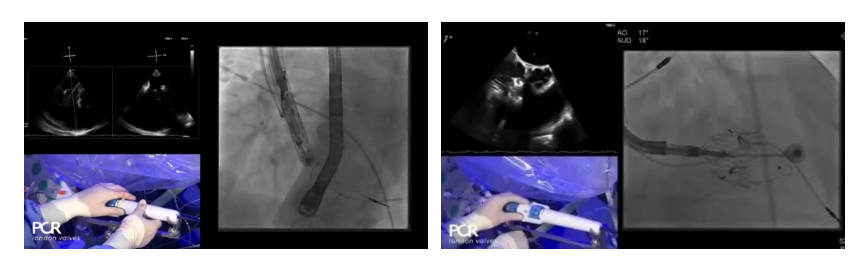

在Thomas Modine教授的線上指導下,德國Mainz中心Ralph Stephan von Bardeleben教授完成了LuX-Valve Plus經(jīng)血管三尖瓣置換系統(tǒng)在其所在中心的首例植入,術后Stephan教授高度贊揚LuX-Valve Plus人工三尖瓣瓣膜“植入過程高度可控,安全有效”。接受治療的是一例82歲的高齡男性患者,術前NYHAⅢ級,因復發(fā)心衰入院,有逾5年的慢性房顫病史。這例患者因特殊的解剖結構以及較大的三尖瓣瓣環(huán),有起搏器植入史,被所有其他經(jīng)導管三尖瓣修復或置換器械的臨床排除在外,因此等了一年半才等到此次LuX-Valve Plus的手術機會,實屬不易。

手術在全麻狀態(tài)下開展,采用經(jīng)右側頸靜脈入路的方式將輸送器送入患者心臟內(nèi),在TEE及DSA引導下調(diào)整輸送器頭端角度,使得輸送器與三尖瓣瓣環(huán)平面垂直。在輸送器進入右心室后釋放室間隔錨定裝置,而后釋放瓣葉夾持件(2個耳片結構)成垂直狀態(tài)。在TEE及DSA確定夾持件固定至三尖瓣葉根部且位于右室側后釋放人工瓣心房側盤片。隨后調(diào)整瓣膜同軸性以及室間隔錨定件位置(貼合室間隔),前推藏針管并固定,進而釋放室間隔錨定裝置,并再次確認瓣膜位置、穩(wěn)定性及同軸性,合攏輸送鞘后撤出輸送器,完成LuX-Valve Plus人工三尖瓣瓣膜的植入。